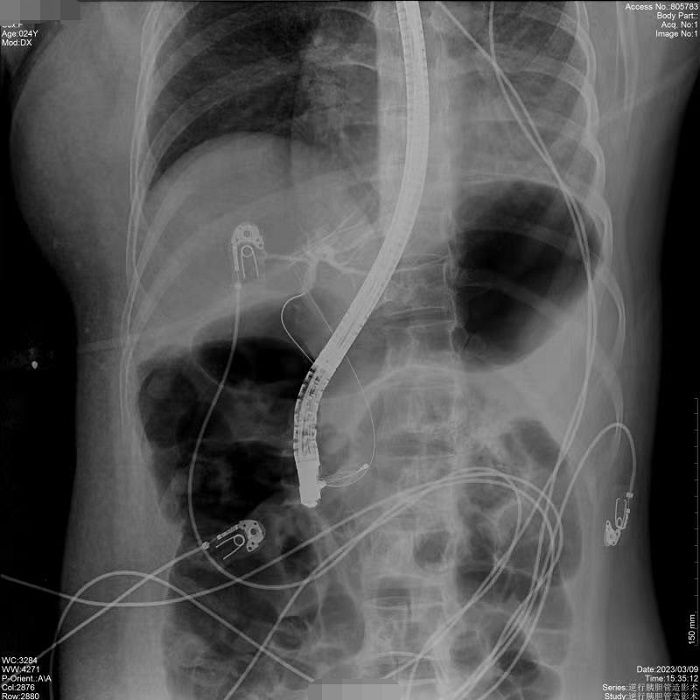

病例1:患者間斷上腹部脹痛4月,經(jīng)磁共振膽道水成像(MRCP)明確為膽總管結(jié)石、膽囊結(jié)石。常規(guī)手術(shù)需要膽總管切開(kāi)取石,考慮其自身的訴求,醫(yī)生決定嘗試為患者做內(nèi)鏡逆行膽管造影術(shù),幫助實(shí)現(xiàn)最小創(chuàng)傷及快速康復(fù)。術(shù)中,通過(guò)十二指腸鏡,將導(dǎo)絲通過(guò)十二指腸乳頭(即膽總管的下端開(kāi)口處)置入膽管內(nèi),在X線透視下注射造影劑造影,完成對(duì)膽總管內(nèi)情況診斷,并在診斷基礎(chǔ)之上完成取石治療。

病例2:患者間歇性上腹部脹痛不適2年,MRCP示膽總管明顯擴(kuò)張,膽囊多發(fā)結(jié)石,醫(yī)生決定應(yīng)用ERCP的手術(shù)方式解除膽道梗阻,通暢引流。在普利德多動(dòng)能動(dòng)態(tài)平板DRF上進(jìn)行ERCP應(yīng)用,成功取出全部結(jié)石,術(shù)后觀察膽汁引流通暢,患者病情平穩(wěn)。